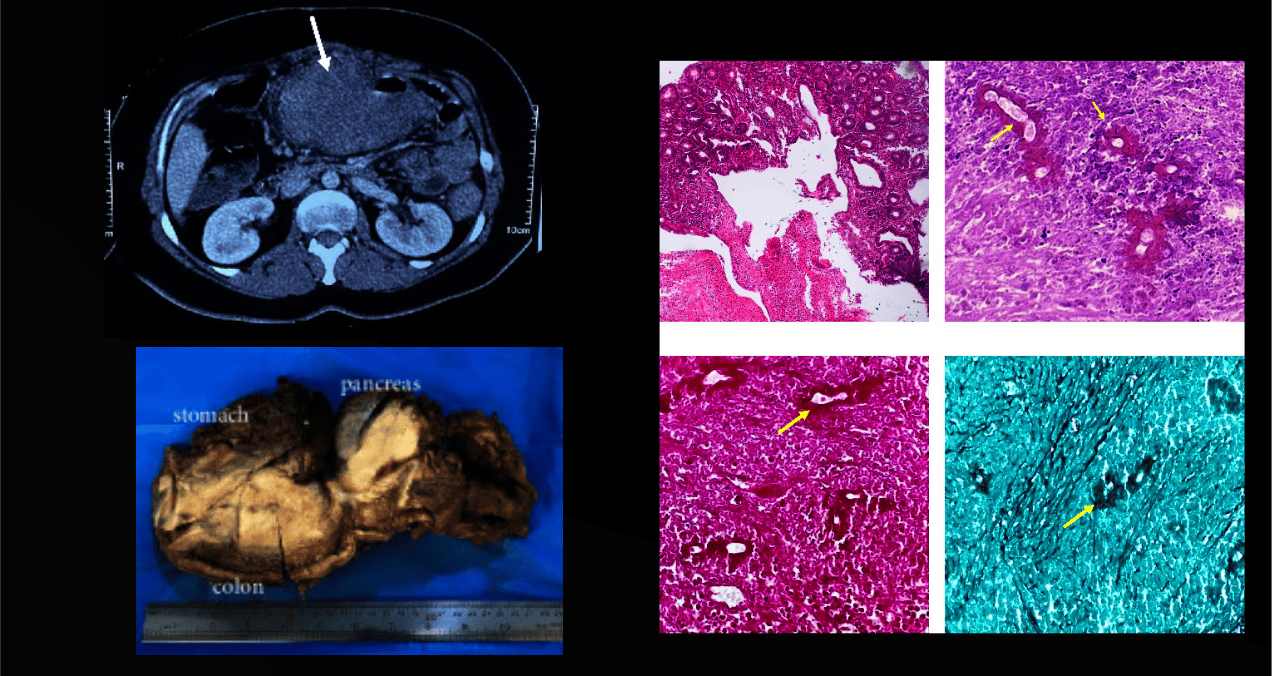

La evaluación macroscópica reveló dos masas bien delimitadas, de consistencia gomosa y aspecto cremoso. La masa más grande, de 17 × 15 × 10 cm, se localizaba en la submucosa del colon y el páncreas, con extensión al estómago. El estudio histológico mostró cambios inflamatorios agudos y crónicos con una reacción predominantemente granulomatosa y un marcado aumento de eosinófilos.

La presencia de hifas fúngicas anchas, de paredes delgadas y aseptadas, rodeadas por el fenómeno de Splendore-Hoeppli (material eosinofílico irradiado), permitió sospechar infección por basidiobolomicosis. El diagnóstico se confirmó mediante tinciones especiales como ácido peryódico de Schiff (PAS) y plata metenamina de Grocott (GMS).

Al revisar las biopsias previas realizadas en otro centro, se identificó un pequeño foco del fenómeno de Splendore-Hoeppli que había pasado desapercibido debido a la falta de familiaridad de los patólogos con esta entidad clínica.

La eosinofilia periférica y tisular es una pista clave, aunque frecuentemente pasa desapercibida. El estándar de oro para el diagnóstico es el cultivo en agar Sabouraud, pero, como en nuestro caso, la baja sospecha inicial y el envío de las muestras en formalina suelen impedirlo, relegando el diagnóstico al hallazgo histológico: hifas anchas aseptadas rodeadas por el fenómeno de Splendore-Hoeppli, confirmado con tinciones especiales (PAS/GMS).